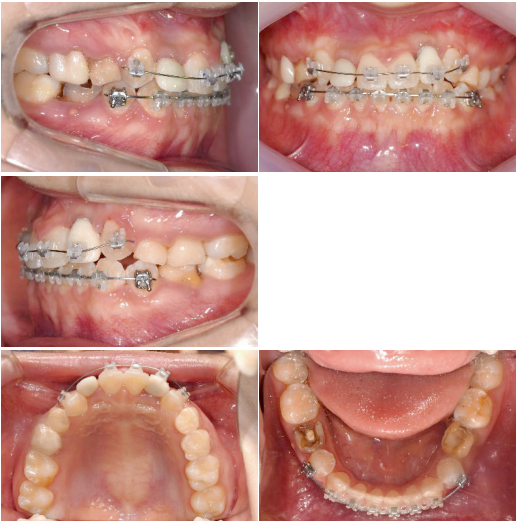

반대교합 수정과 측절치 임플란트 식립및 temporary crown을 이용한 보철수복이 이루어졌습니다. 양측 견치의 수직적 차이가 조금 더 명확해졌습니다.

Occlusal canting을 수정하기 위해 상악 좌측 임플란트보철물에 bracket을 기울여 붙여서 slot의 방향대로 archwire가 삽입되었을때 좌측 견치는 정출되고 우측 견치는 함입되도록 하였습니다.

Slot의 방향에 맞춰 전치부 occlusalcanting이 개선되었습니다. 좌측견치의 정출이확연히 눈에 띕니다.